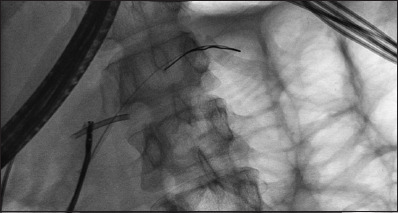

背景:胰腺支架近端移位是一个不常见但重要的问题,它会带来疼痛和胰腺炎的风险。对于内窥镜医生来说,这通常是一个具有挑战性的情况,10%的病例需要手术切除。方法:对2010年1月至2019年12月在印度北部一家三级医疗中心进行的支架移除手术进行了10年的回顾性研究。结果:本组共16例(平均年龄39.52岁,男性13例[81.25%])行近端移位胰内支架(pmps)。13例(81.25%)患者胰管扩张,3例(18.75%)患者胰管未扩张。在大多数患者中,pmps位于膝(50%),62%长度为10 cm。3例(18.75%)患者支架碎片化,其余13例(81.25%)患者支架原位完整。12例(75%)患者可以完全取出PPMS和支架碎片,大多数(50%)患者使用抓钳。在支架碎片化和定位困难的患者中(n=3),胰镜辅助技术可将支架或碎片取出。3例患者pmps无法检索:所有这些失败都发生在我们单位没有SpyGlass胰镜的研究期间。2例患者(12.5%)报告术后疼痛对静脉镇痛药有反应。结论:内镜下取下近端移位支架,结合技术和附件是安全有效的。胰镜检查提高了成功率。支架移除很少需要手术。

Results: Sixteen patients (mean age 39.52 years, 13 [81.25%] males) with proximally migrated pancreatic stents (PMPSs) were studied. Thirteen (81.25%) patients had a dilated pancreatic duct (PD) and 3 (18.75%) had a non-dilated PD. In the majority of patients, the PMPSs were located at the genu (50%), while 62% were 10 cm in length. Three (18.75%) patients had fragmented stents, whereas the remaining 13 (81.25%) had intact stents in situ. Complete retrieval of the PPMS and stent fragments was possible in 12 (75%) patients, with grasping forceps being used in the majority (50%). In patients with fragmented stents and difficult locations (n=3), pancreatoscopy-assisted techniques resulted in the retrieval of the stent or fragments. PMPSs could not be retrieved in 3 patients: all these failures were during the study period when a SpyGlass pancreatoscope was not available in our unit. Two patients (12.5%) reported post-procedural pain that responded to intravenous analgesics.